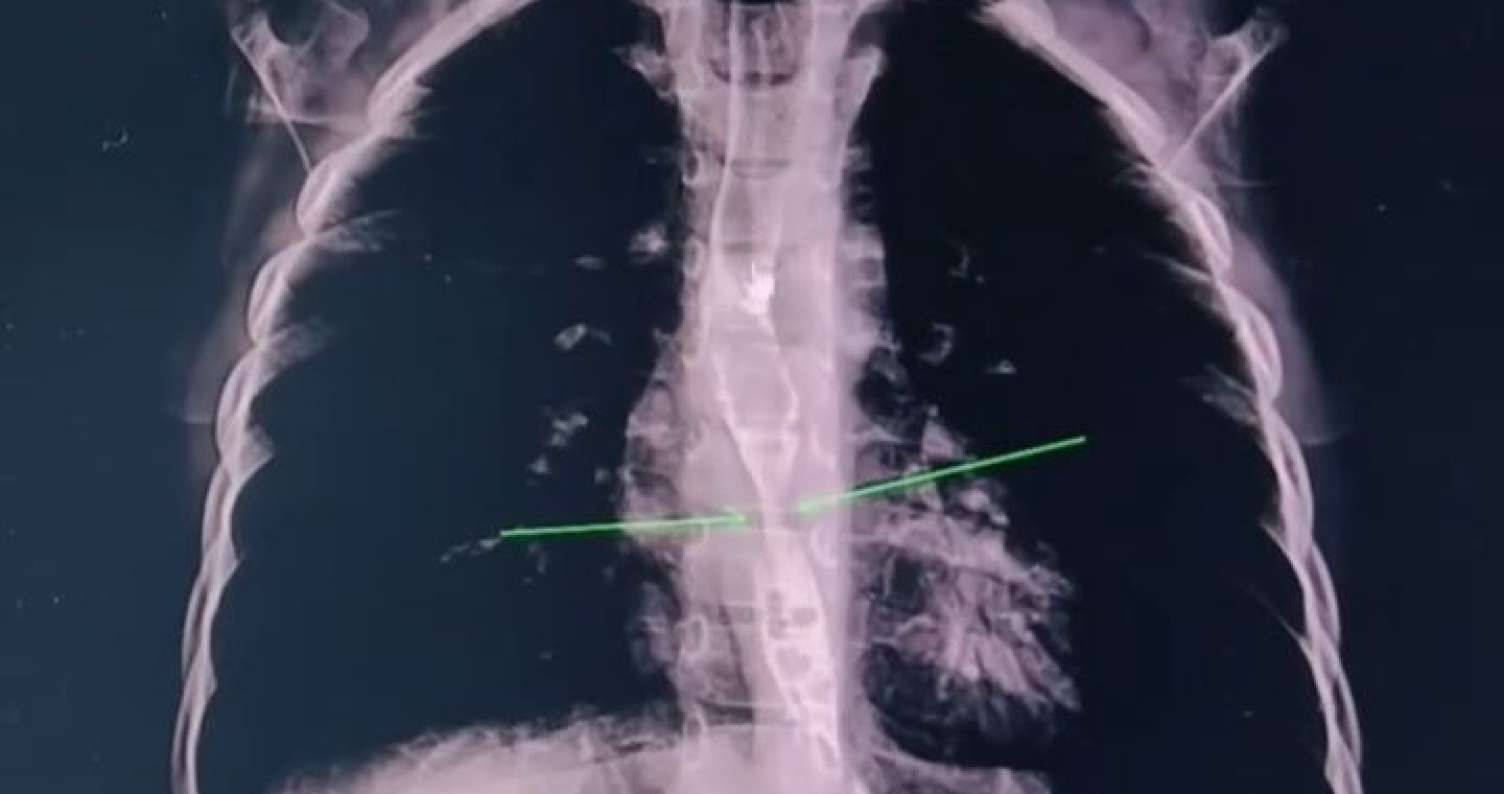

Həkimlər